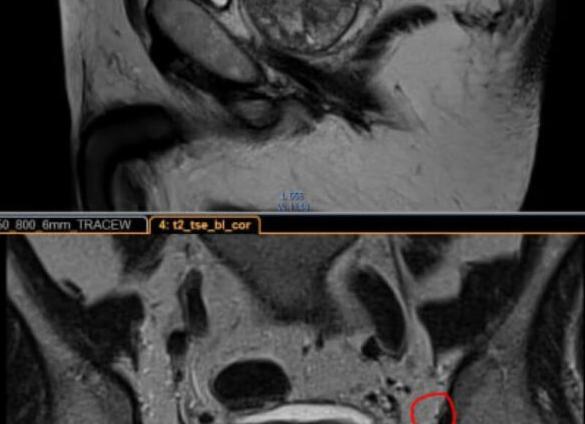

Предстательная железа располагается в малом тазу, под мочевым пузырем, состоит из двух половин, между которыми проходит мочеиспускательный канал. Предстательная железа, по данным томограммы, подразделяется на периферическую, центральную и фибромускулярную зоны.

По данным МРТ каждый патологический процесс выбирает определенную область железы. Высокая чувствительность и специфичность делает методику уникальной. Позволяет обнаружить патологическое состояние и соотнести к определенной нозологической группе. Каждая ткань при МР-исследовании имеет свои характеристики – интенсивность сигнала (гиперинтенсивный – ярко-белый, гипоинтенсивный – ярко-черный, изоинтенсивный — серый) в разных программах (Т1, Т2).

В норме в программе Т2 периферическая зона светлая, центральная – темная, фибромускулярная – черная.

По Т1 периферическая и центральная зоны – серые, фибромускулярная – черная.

Острый простатит

Мрт простаты при остром заболевании показывает, что поражается периферическая зона. Сопровождается локальным или распространенным увеличением правой или левой доли. По цвету периферическая зона из умеренно-светлой переходит в ярко-белую. Дополнительно реагируют простатические лимфоузлы, размер их увеличивается, интенсивность сигнала изменяется.

Хронический простатит

На фоне лечения отечность периферической зоны снижается, соответственно интенсивность сигнала из ярко-белой переходит в серую по Т2. Длительный простатит приводит к нарушениям этой зоны. Поэтому часто даже после терапии периферическая зона не становится светлой, как у здоровых мужчин. Она останется однородно или фрагментарно серой.

Доброкачественная гиперплазия

Доброкачественная гиперплазия предстательной железы (ДГПЖ) – патологический процесс, сопровождающийся разрастанием центральной зоны. В норме отмечаются равные пропорции железистой и стромальной ткани.

При заболевании происходит резкое увеличение объема с формированием отдельных узлов (аденомы). Рост может быть настолько выраженным, что она начинает выбухать в полость мочевого пузыря. Общий размер предстательной железы при этом также увеличивается. ПСА становится выше 4 нг/мл.

Аденокарцинома простаты

Опухоли простаты могут быть в центральной и периферической зоне, но при МРТ наиболее хорошо диагностируются именно в периферической. Образования по сигналам темнее, чем периферическая зона по Т2. Форма и размер – вариабельны. Совестно с врачами урологами была разработана унифицированная система стадирования рака (PI-RADS).

Сложность для диагностики представляют случаи выявления опухоли на фоне хронического простатита. С целью подтверждения наличия образования рекомендуется проводить томографию с внутривенным контрастированием.